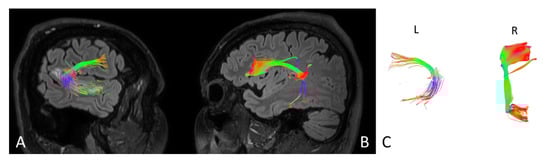

| Parameters | Left side | Right side | Left side | Right side |

| Number of fibres | 160 | 205 | 185 | 208 |

| Volume of tract [mm2] | 1125 | 18440 | 1280 | 18559 |

| Length of tract [mm] | 75.5 | 88.0 | 86.4 | 89.0 |

| FA | 0.715 | 0.885 | 0.785 | 0.880 |